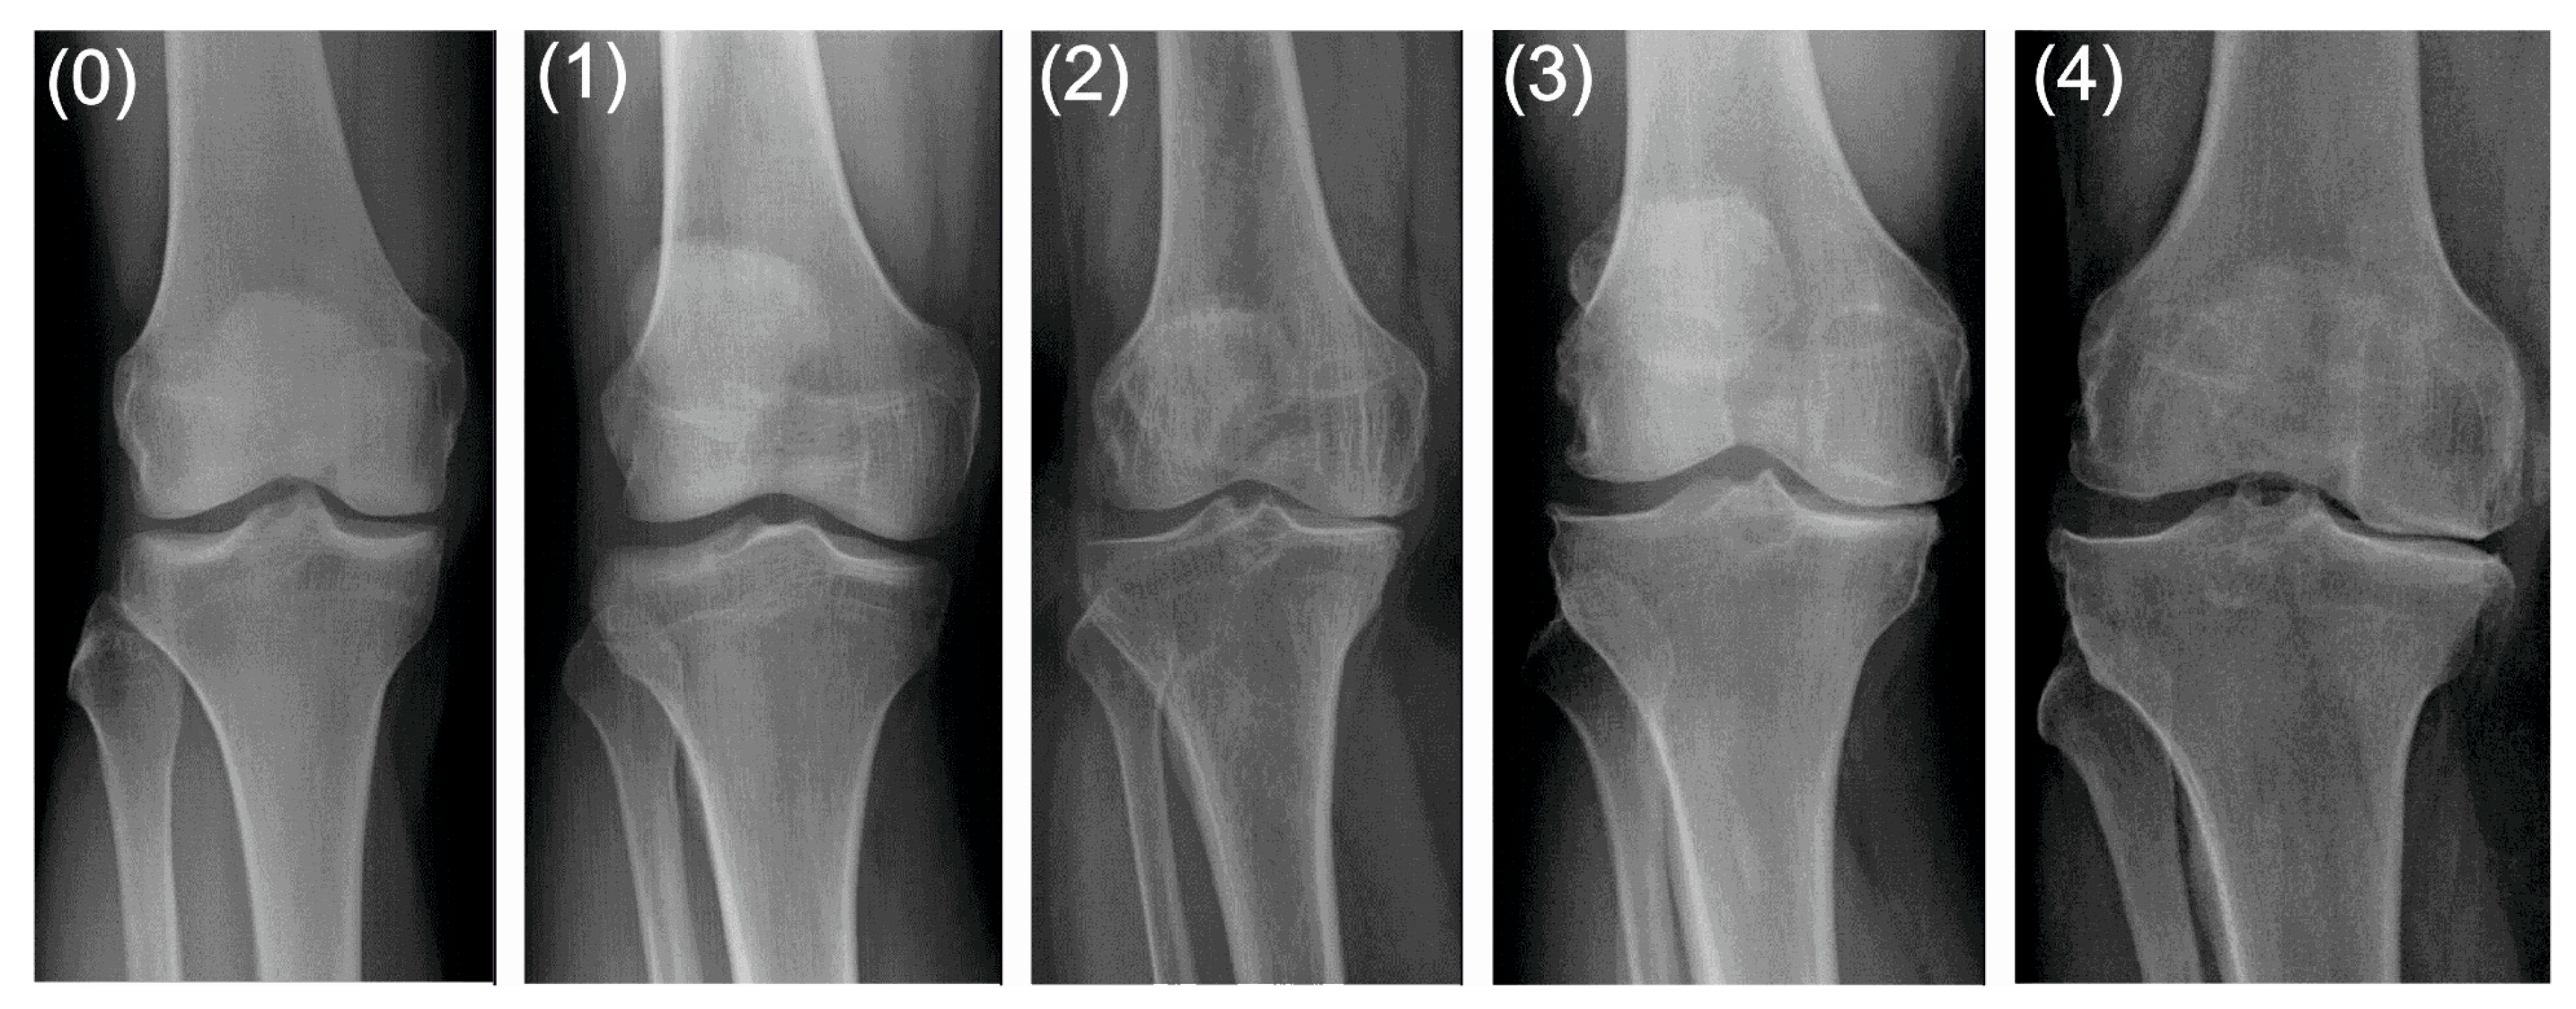

The control group comprised 14 patients with grade 0 and 11 patients with grade 1 degenerative changes on the K–L scale, whereas 39 and 18 patients from the study group were diagnosed with grade 3 and 4 degenerative changes on the K–L scale, respectively [11]. Examples of X-rays are presented in Figure 2.

Figure 2.

Grades of degenerative changes on the Kellgren-Lawrence scale: 0—none, 1—doubtful, 2—minimal, 3—moderate, 4—severe.